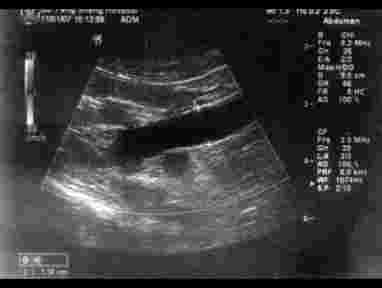

第123例附图3 左输尿管明显扩张积水

第123例附图4 左输尿管末端均匀低回声,肿物充满管腔,完全堵塞左输尿管